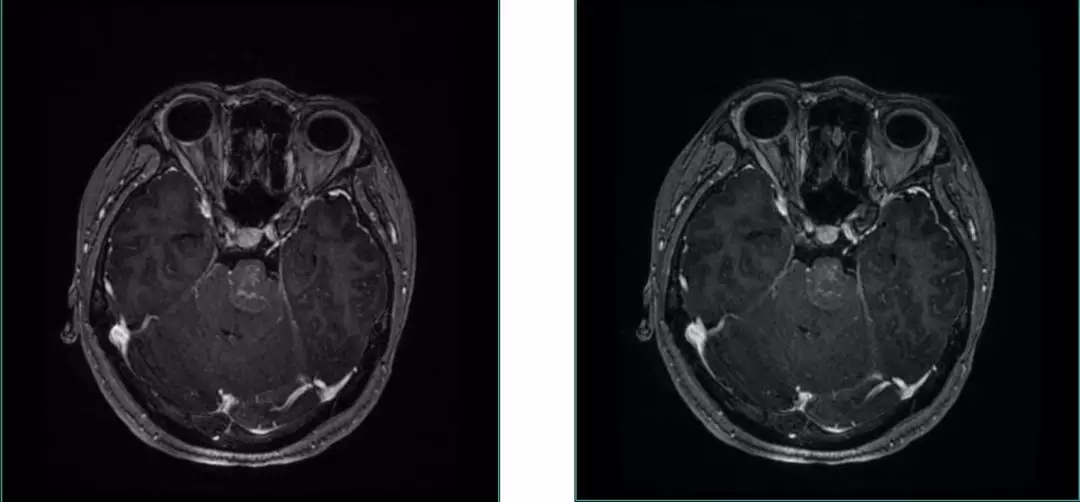

• 22y, Female headache , double Vision for 4 m;

• Examination:GCS 15 scores;abducens nerve palsy

• MRI Images:Reveals occupying lesions in pre-pon cistern, tumor with a upper clivus extension imbedding into brainstem from anterior.  Part of clivus bone is erosion.

Pre-op MRI Contrast